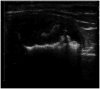

Practical relevance: Uroliths occur commonly in the bladder and/or urethra of cats and can be lifethreatening if urethral obstruction occurs. Calcium oxalate accounts for 40-50% of urocystoliths and these stones are not amenable to medical dissolution; therefore, removal by surgery or minimally invasive techniques is required if uroliths must be treated. Medical protocols for prevention involve decreasing urine saturation for minerals that form uroliths.

Basic concepts: In order to develop rational and effective approaches to treatment, abnormalities that promote urolith formation must be identified, with the goal of eliminating or modifying them. It is important, therefore, to understand several basic concepts associated with urolithiasis and the factors that promote urolith formation that may be modified with medical treatment; for example, the state of urinary saturation, modifiers of crystal formation, potential for multiple crystal types, and presence of bacterial infection or urinary obstruction.